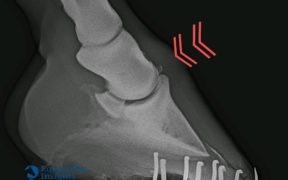

06 dicembre 2019 #news Le patologie osteocondrali giovanili hanno un impatto importante sugli equini e riguardano gli apparati muscolo-scheletrici del cavallo giovane. Molti allevatori si imbattono in questo problema quando ad esempio, con le prime lastre, scoprono uno o più “chip” o cisti nelle articolazioni di un puledro, il quale tuttavia non ha mai presentato zoppie. L’osteocondrite […]